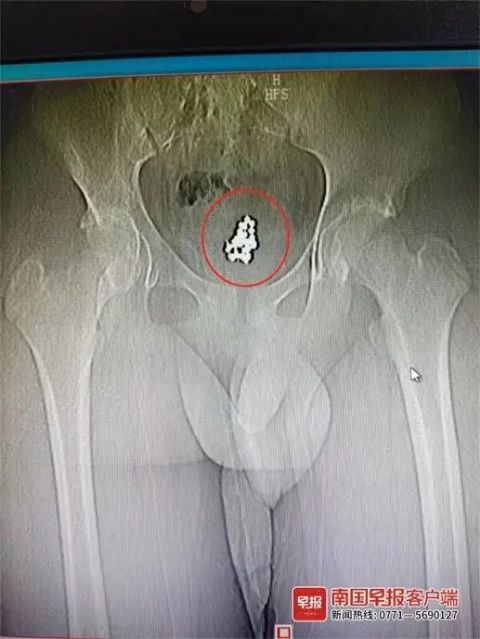

经B超检查,系统提示小安膀胱部位有结石。但之后进一步进行CT检查时,医生发现小安膀胱里有一颗颗形状规整的异物,于是判断这么整齐的影像不像是结石,倒像是患者自行塞进去的异物。

图片

▲在小安膀胱内待了2年的磁力珠。院方供图